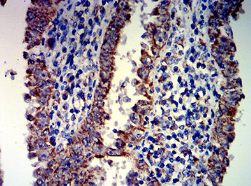

IHC    1/200-1/1000